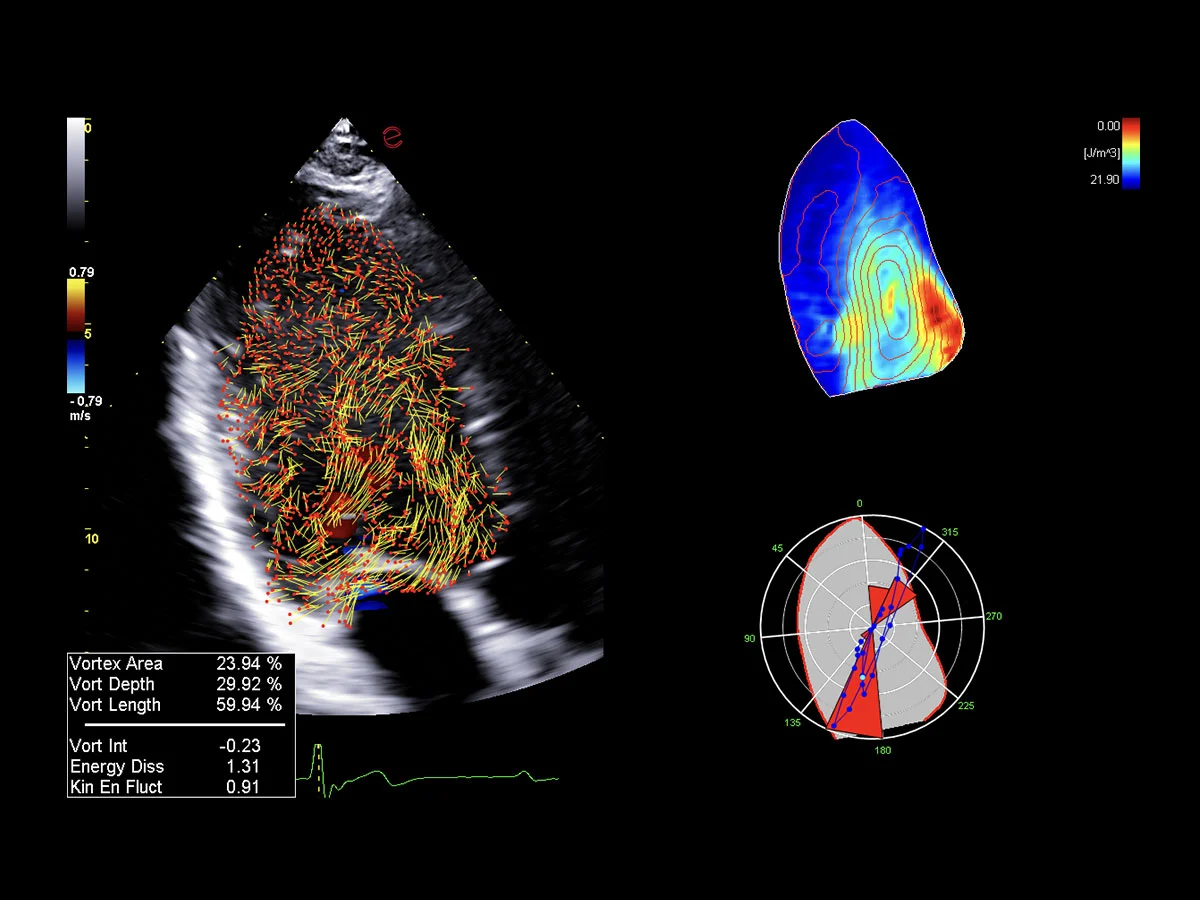

Innovative hemodynamic assessment with HyperDoppler

Esaote’s HyperDoppler technology provides an advanced visualization of intracardiac blood flow dynamics, offering clinicians an intuitive understanding of complex hemodynamics that goes beyond conventional Doppler imaging. By generating real-time vector maps, streamlines, and vortex formations, HyperDoppler enables the detailed assessment of diastolic function, ventricular dyssynchrony, and valvular abnormalities.

This unique flow visualization supports earlier detection of subtle dysfunction, particularly in challenging cases such as heart failure, prosthetic valve evaluation, and structural heart disease. HyperDoppler’s zero-click, visually rich interface enables faster, more comprehensive exams, allowing cardiologists to make more informed clinical decisions.